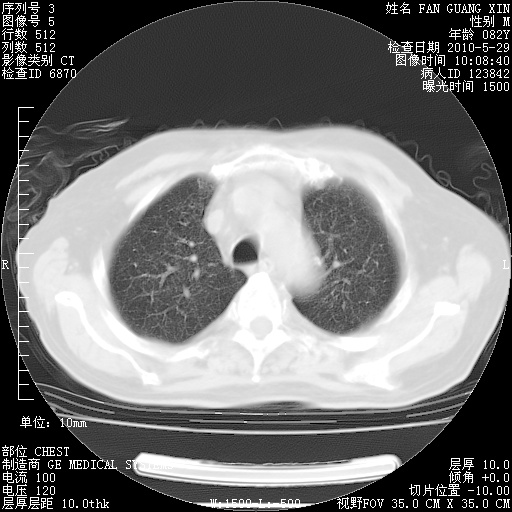

再治疗10天后的肺部CT

肺部体征:呼吸25次/分,心率100次/分,呼吸音增粗。无干湿罗音。

血常规:15.36×10 [sup]9[/sup]/L  N0.92  L0.036  M0.045 ESR 27mm/h。

血生化:白蛋白33.30g/L  球蛋白23.67g/L  CRP 32.82mg/L 肝肾功能正常。电解质正常。

从白细胞总数和中性比例看好像合并感染。肺部纹理好像比上次多,支气管炎?其他感染?